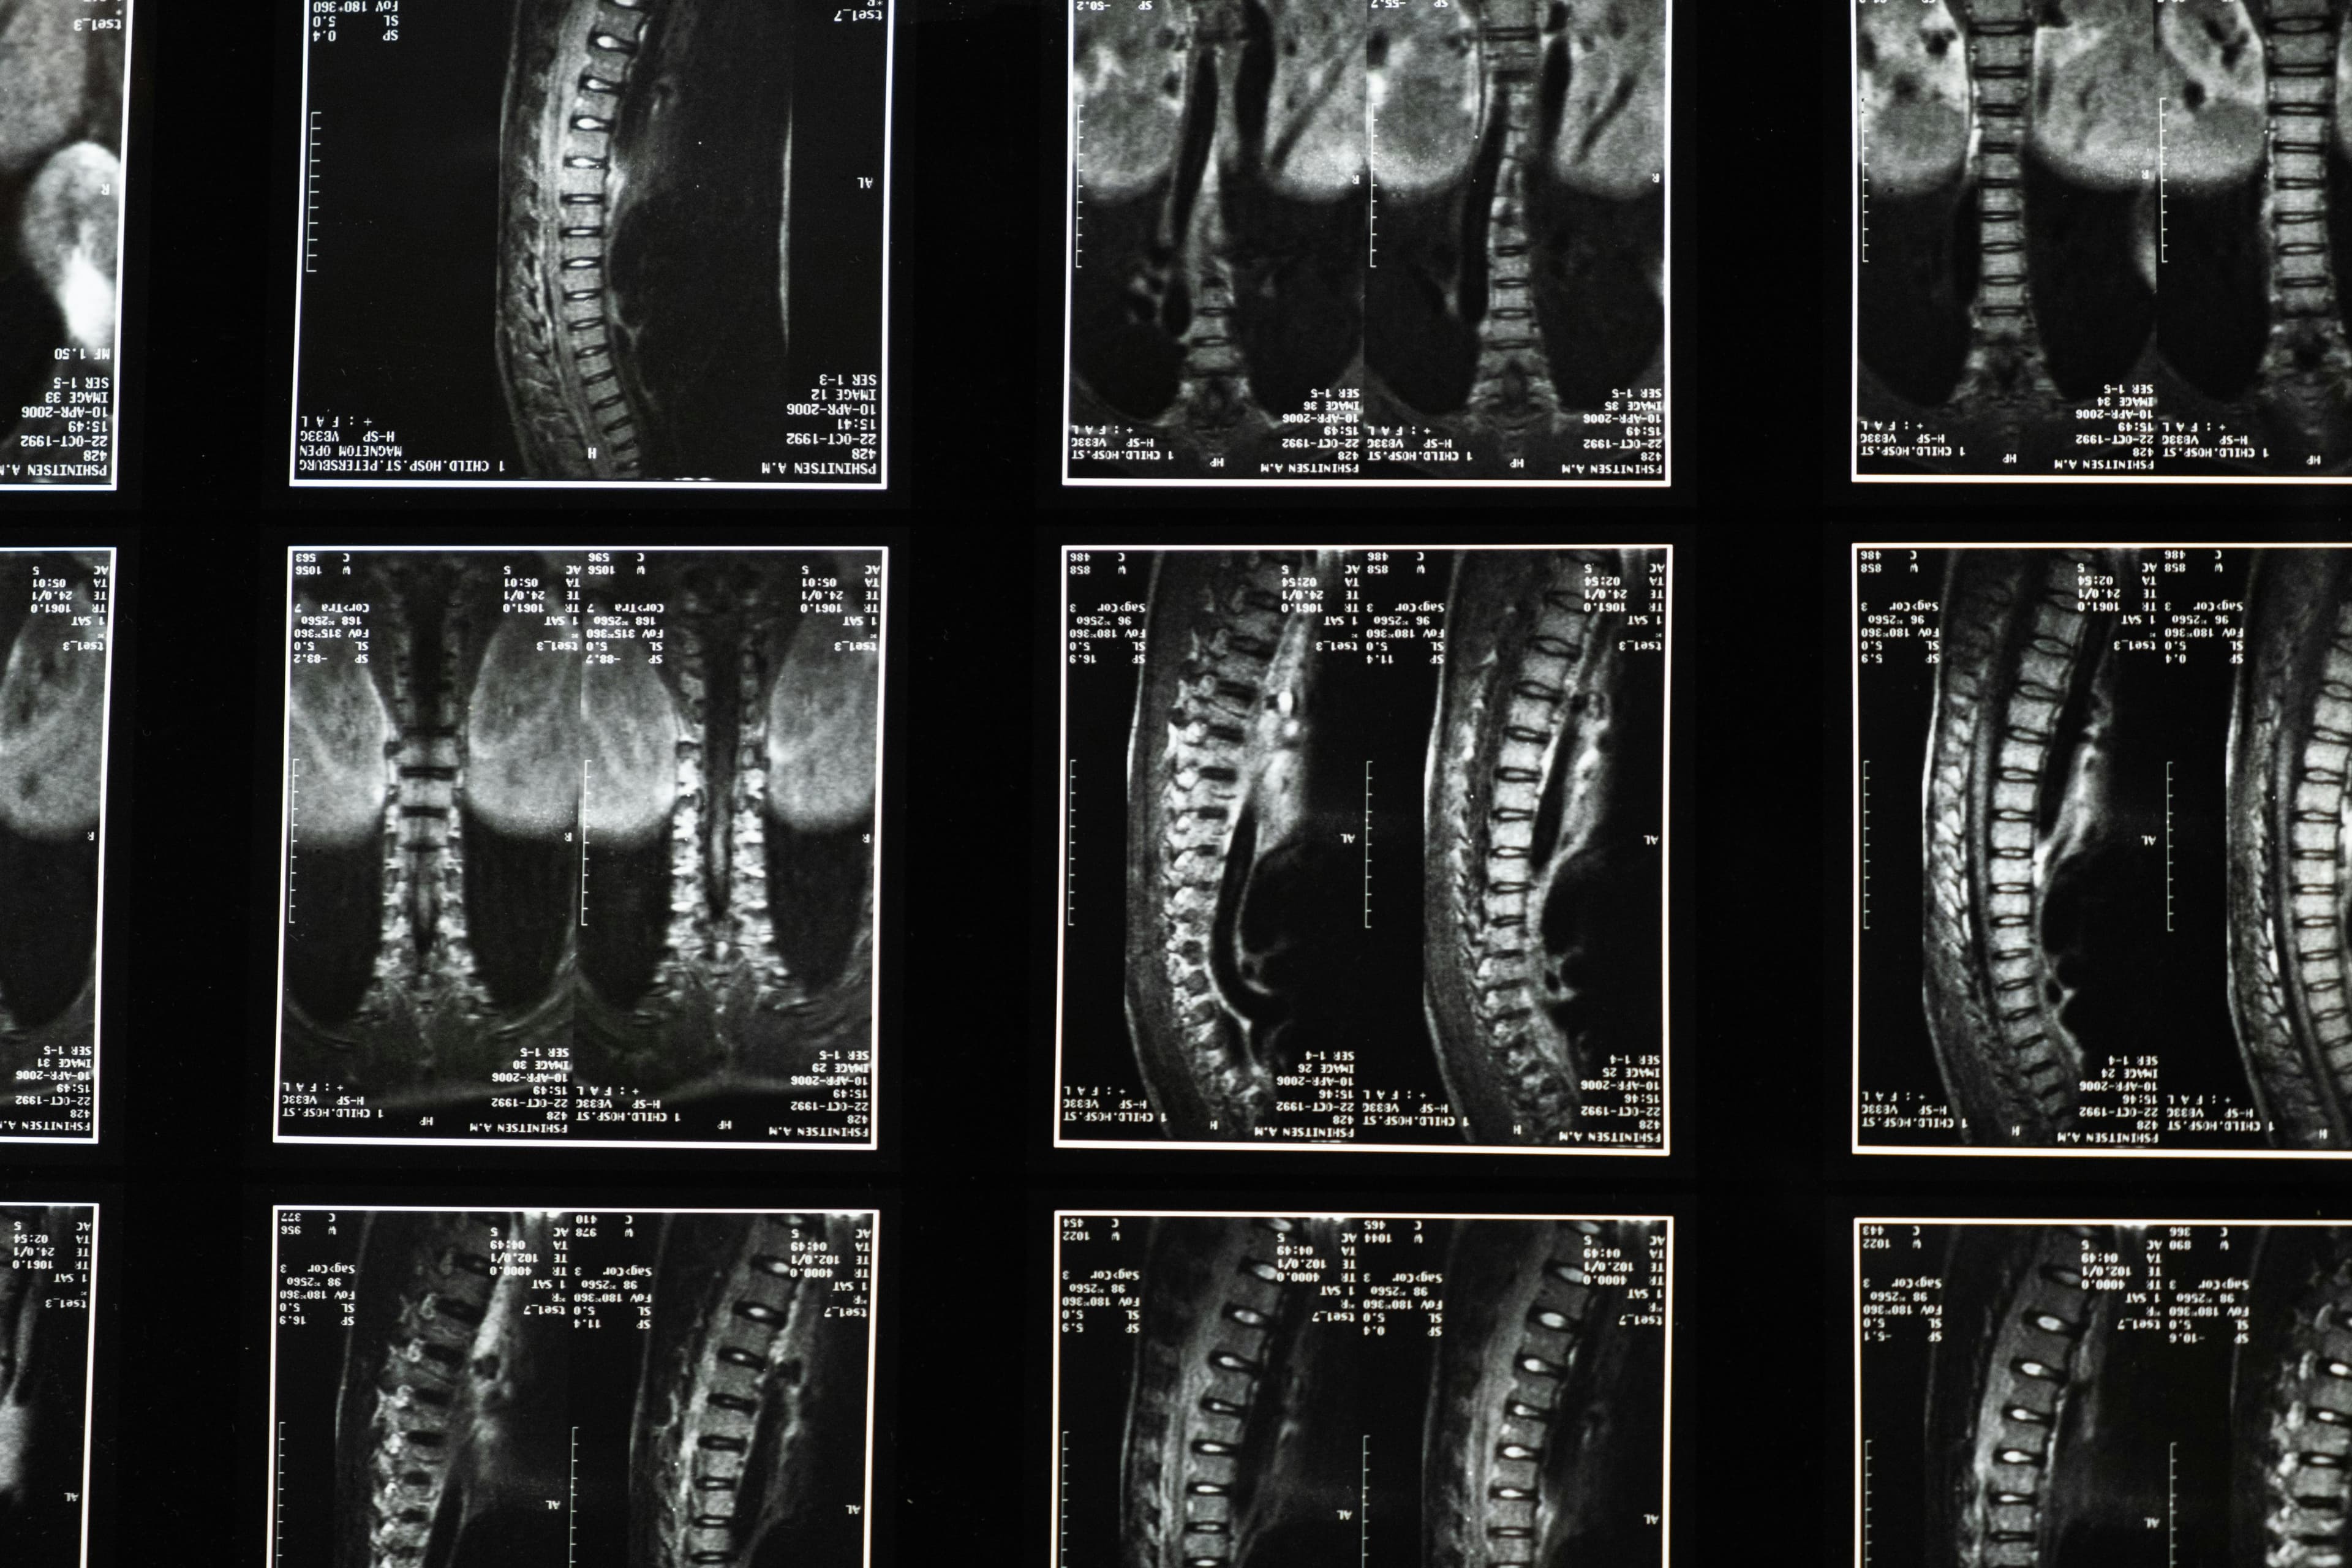

Understanding Lumbar Spondylosis

Lumbar spondylosis is characterized by wear and tear of the vertebrae and discs in the lower back. It's a common condition, especially among older adults, often leading to pain, stiffness, and reduced mobility. According to a recent study, it most commonly affects the lumbar 4-5 and lumbar 5-sacral 1 vertebrae, accounting for approximately 95% of cases.